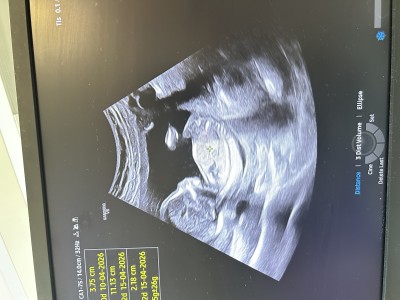

30 Kasım 2025 Hamilelik Dönemi Genel kategorisinde (4 puan) sordu

rica etsem tahminde bulunabilir misiniz 🙏🏻

Kıza benziyor canım

Erkeğe benziyor nub una gore